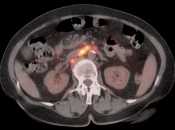

Metastatic Disease:

- Direct invasion of adjacent structures.

- Lymphatic spread to pelvic and retroperitoneal lymph nodes.

- Hematogenous spread, often to lungs, liver, and bone.